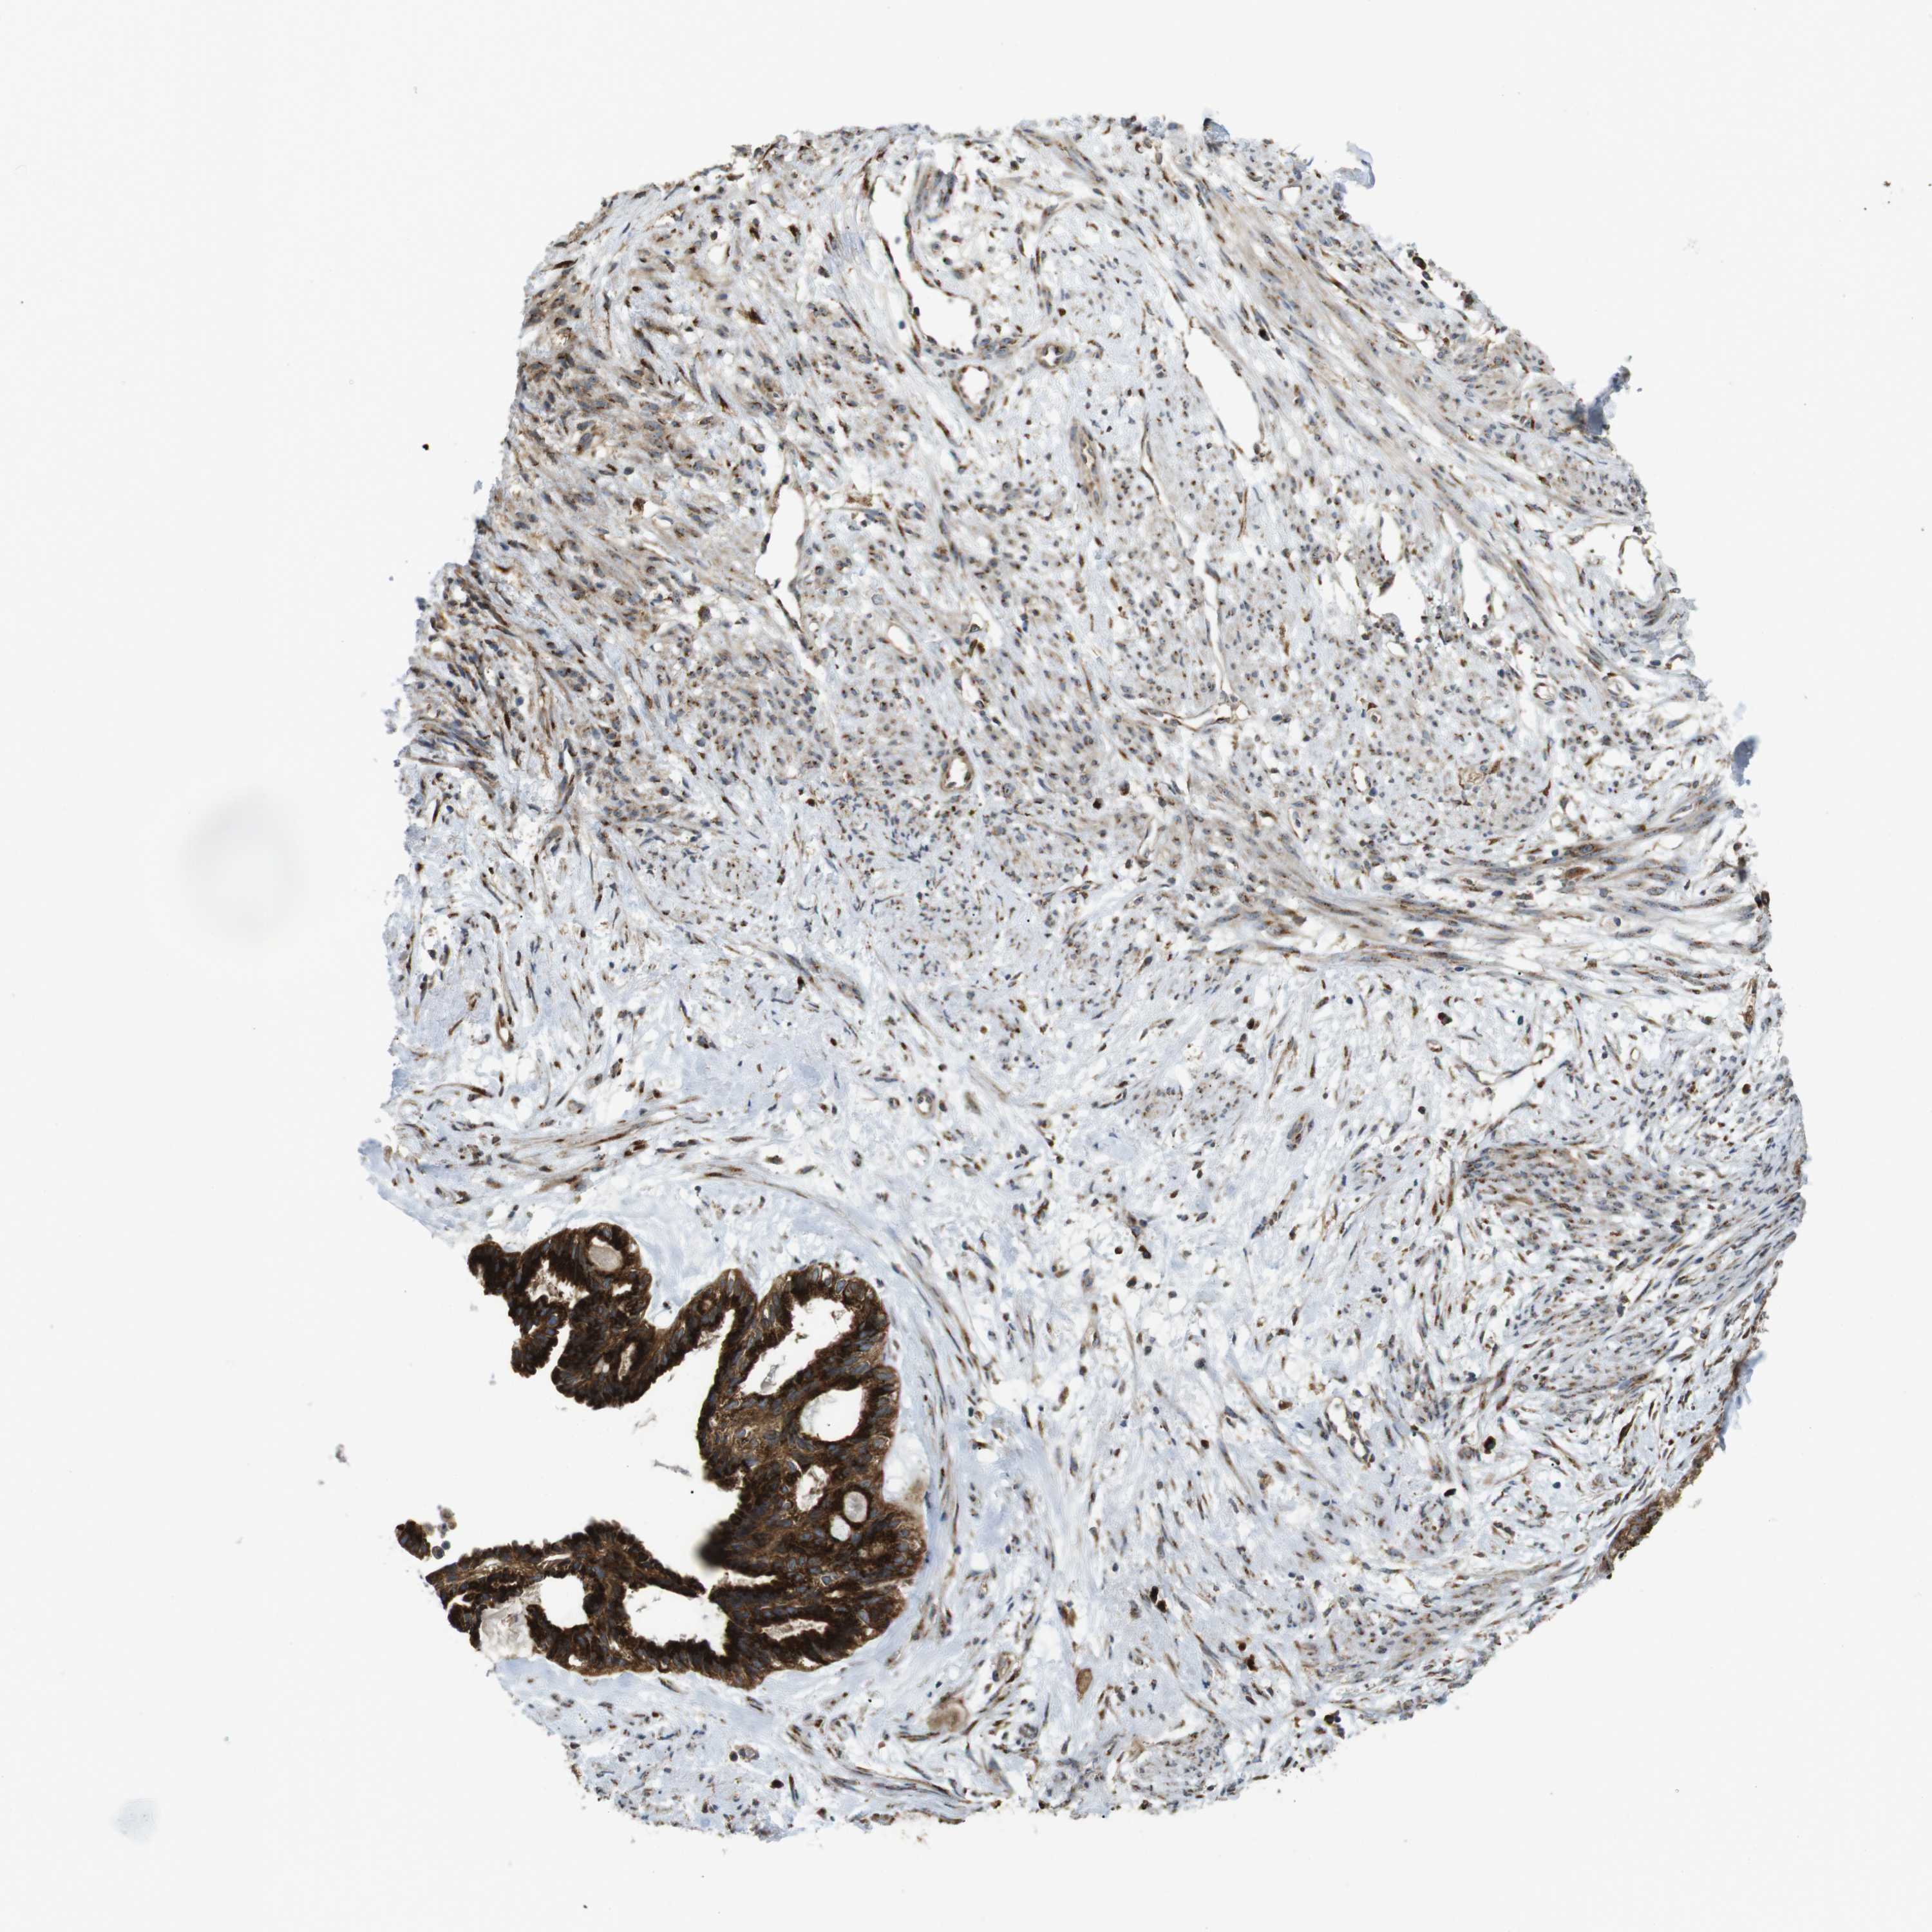

CERVICAL CANCER - Protein expressioni

A mouse-over function shows sample information and annotation data. Click on an image to view it in a full screen mode. Samples can be filtered based on level of antibody staining by selecting one or several of the following categories: high, medium, low and not detected. The assay and annotation is described here.

Note that samples used for immunohistochemistry by the Human Protein Atlas do not correspond to samples in the TCGA dataset.

Antibody stainingi

Antibody staining in the annotated cell types in the current human tissue is reported as not detected, low, medium, or high, based on conventional immunohistochemistry profiling in selected tissues. This score is based on the combination of the staining intensity and fraction of stained cells.

Each image is clickable and will lead to virtual microscopy that enables deeper exploration of all samples and also displays staining intensity scores, fraction scores and subcellular localization as well as patient and tissue information for each sample.

Antibody HPA014476

Antibody HPA058645

Staining

High

Medium

Low

Not detected

Intensity

Strong

Moderate

Weak

Negative

Quantity

>75%

75%-25%

<25%

None

Location

Nuclear

Cytoplasmic/membranous

Cytoplasmic/membranous,nuclear

Squamous cell carcinoma, NOS

Adenocarcinoma, NOS